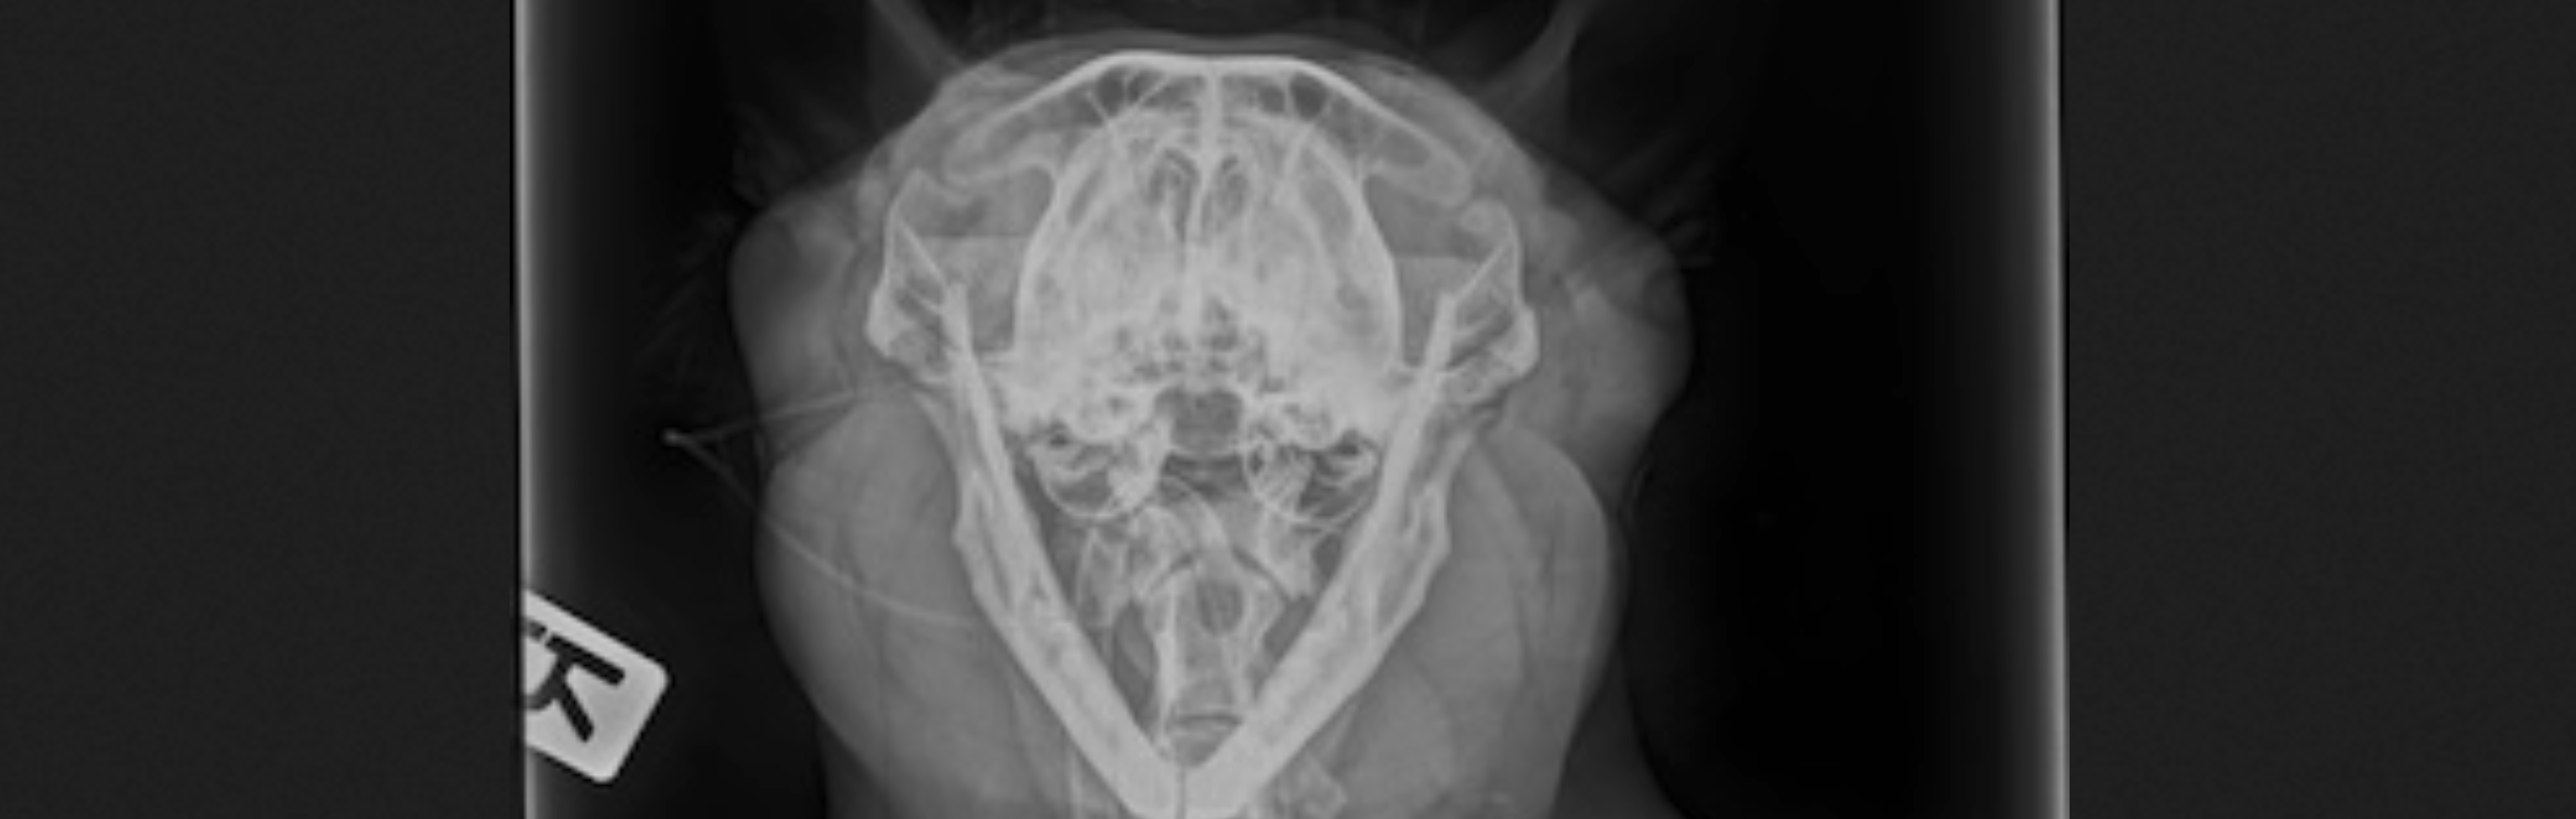

HNO=Hals-Nasen-Ohren-Erkrankungen sind bei Tieren nicht selten. Manche Rasse sind sogar häufig betroffen. Symptome sind folgende: Niesen, Schnupfen, Atemgeräusche, Schnarchen, Husten, Atemnot, Hitzeempfindlichkeit und Belastungsintoleranz.

Zur Diagnostik sind oftmals weiterführende Untersuchungen nötig.